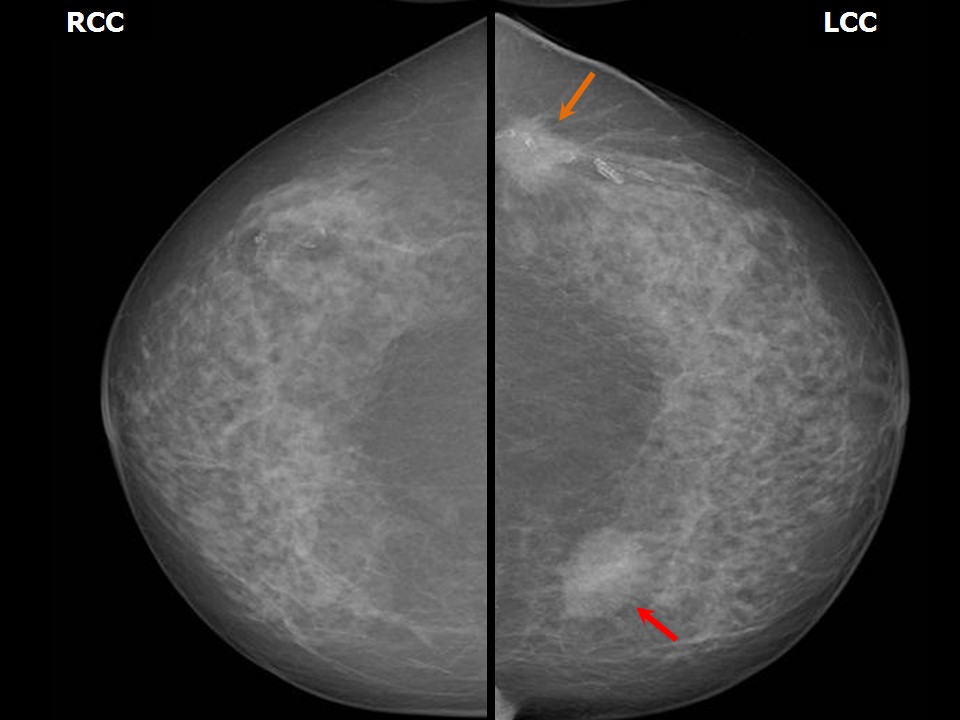

Феномен гипердиагностики в маммографии: примеры и иллюстрации

Раздел: Образы вокруг